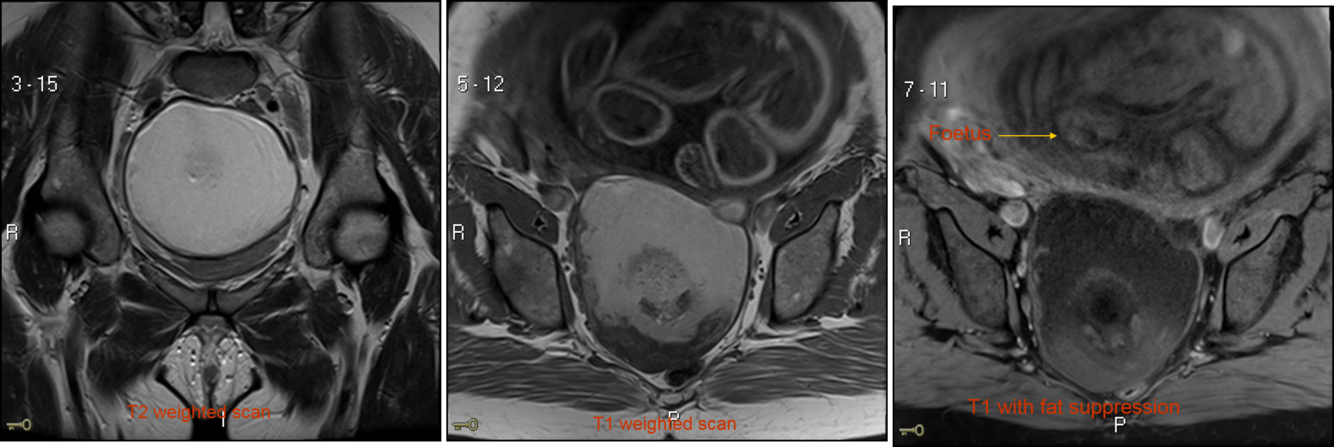

Describe the 2 main different types of MRI scan and what they look at

T1 images – 1 tissue type is bright – FAT e.g. subcutaneous fat (SC fat) and bone marrow

T2 images – 2 tissue types are bright – FAT and WATER e.g. CSF

Describe the appearnace of dermoid cysts on MRI

They can contain an admixture of many types of tissue, but most contain a large amount of fat.